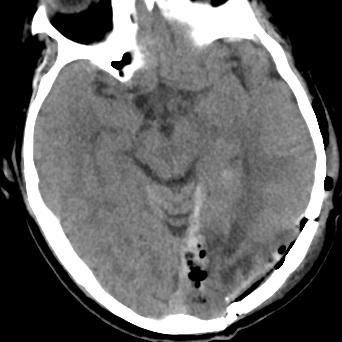

该病人在我院通过颅脑磁共振增强检查出左侧大脑镰旁占位性病变,来我院要求手术治疗,在完善相关术前检查时,患者的胸部CT结果却给我们带来诸多疑惑。

看到这样的胸部CT结果,神经外科医师做的第一件事就是再次核查患者流行病学史,反复确认新冠肺炎检查报告均为阴性后再请呼吸科、感染科医师会诊,会诊结合患者胸部CT均有考虑粟粒状肺结核灶可能,但患者入院后血常规、生化、血沉、痰找抗酸杆菌检查正常,结核分支核酸检测弱阳性。